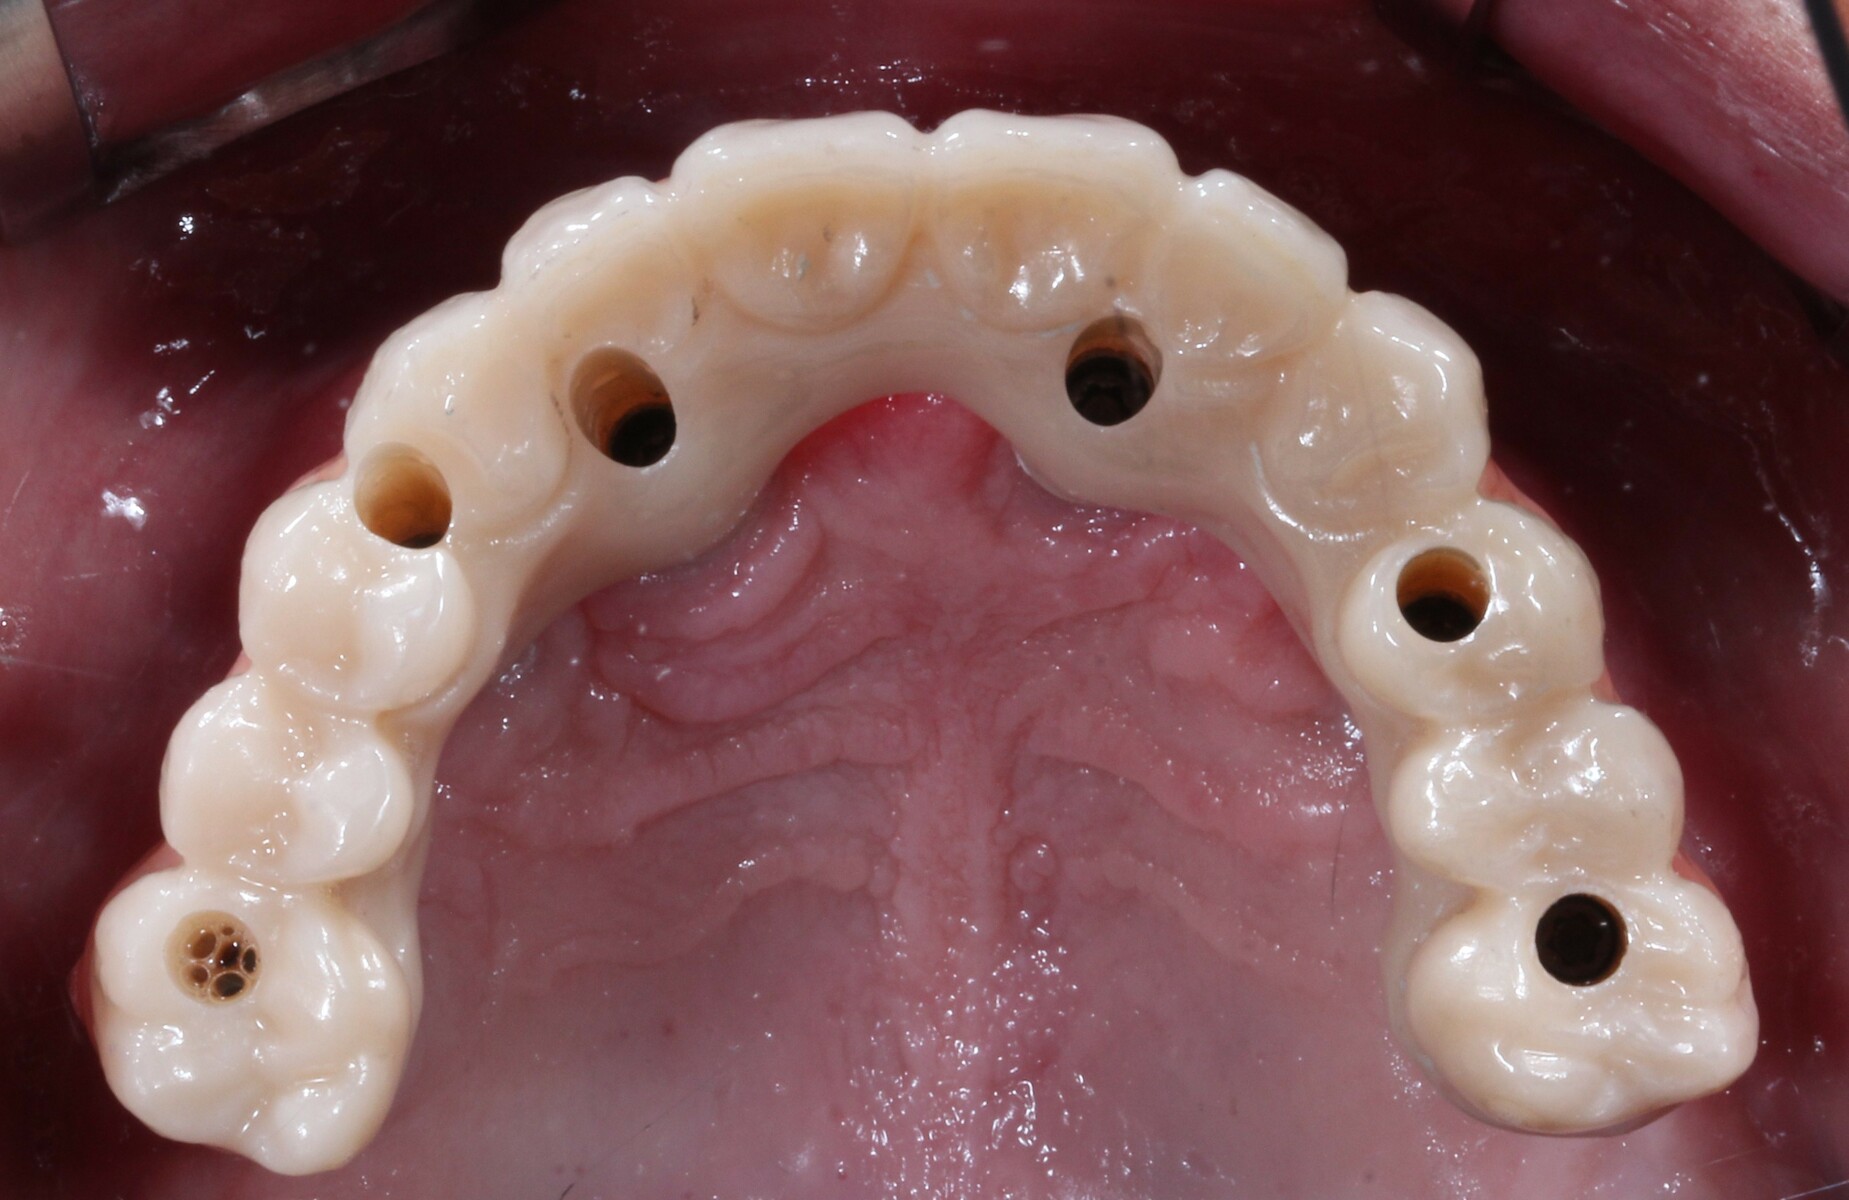

Complete mouth implant rehabilitation with a zirconia ceramic system A Dental Rehabilitation With Zirconia Zirconia is a material widely used in fixed prosthodontics, whether on natural teeth or on implants, with excellent results over time. Zirconia is a suitable choice for prosthetic rehabilitation in crowns and veneers due to its white color, adaptability, exceptional fracture resistance, and flexural. This clinical report describes a complete mouth. The dental ceramic with the highest reported mechanical properties. Dental Rehabilitation With Zirconia.

Implant rehabilitation with zirconia teeth 3StepSmiles Dental Rehabilitation With Zirconia Zirconia is a material widely used in fixed prosthodontics, whether on natural teeth or on implants, with excellent results over time. The dental ceramic with the highest reported mechanical properties is zirconia. The dental ceramic with the highest reported mechanical properties is zirconia. Zirconia is a suitable choice for prosthetic rehabilitation in crowns and veneers due to its white color,. Dental Rehabilitation With Zirconia.

Prosthesis Free FullText FullArch, ImplantFixed Complete Dental Rehabilitation With Zirconia The dental ceramic with the highest reported mechanical properties is zirconia. This clinical report describes a complete mouth. Regarding the use of zirconia for isfcdps, the 2018 iti consensus report stated that “implant This clinical report describes a complete mouth implant rehabilitation with computer. The dental ceramic with the highest reported mechanical properties is zirconia. Zirconia is a material widely. Dental Rehabilitation With Zirconia.